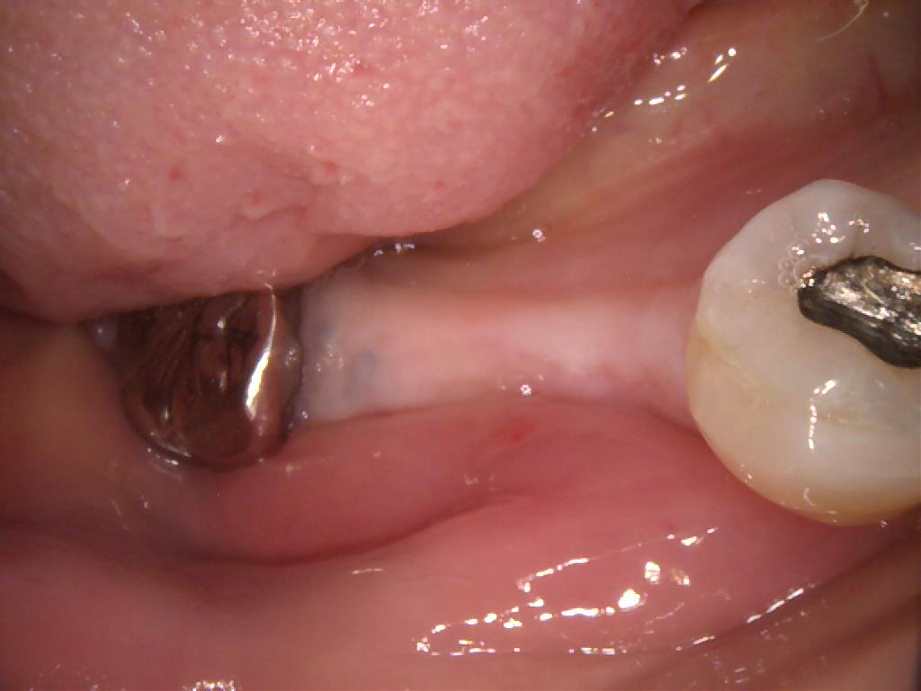

インプラント治療の実際の症例

CASE – 01

before

▶︎

▼

after

| 主訴 | 左下、歯がなくてかめない |

| 担当医 | 山口 和善 |

| 治療期間 | 6か月 |

| 治療内容 | ①CT撮影、型取り、治療計画やリスクの説明 ②手術用ガイドの試適 ③1次手術 ④消毒 ⑤抜糸 ⑥2次手術 ⑦上部構造型取り ⑧上部構造装着 |

| 合計通院回数 | 8回 |

| 治療費 | CTによる診査診断…11,000円 1次手術…186,000円 2次手術…22,000円 手術用ガイド…44,000円 上部構造…99,000円 合計(インプラント1本)…362,000円 |